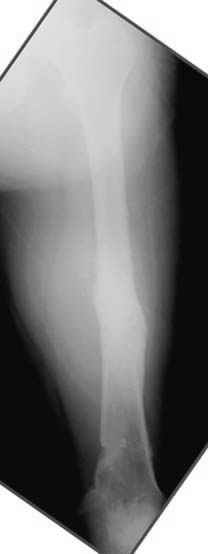

N3 рисунок окончательный снимок, после операции моя рентгенограмма должен выглядеть примерно как эта картина. На N4 снимке клин перед удалением; N5 послеоперации 3 нед.; N6 окончательная рентгенограмма.

пластическая модель; и коррекция бедра аппаратом Илизарова.